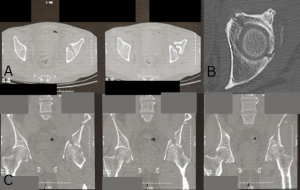

Examination at the time revealed 4/5 weakness of the supraspinatus, tenderness over the LHBT and AC joint, and positive Neer, Hawkins, and cross-body adduction signs. Surgical treatment options were discussed and the patient elected to proceed with a right shoulder arthroscopy, RTC repair, distal clavicle excision, decompression, and biceps tenodesis. Informed consent was obtained. The surgical technique was performed with the patient in beach chair position under general anesthesia. A posterior arthroscopic portal was created, and no changes were noted on the glenoid or humeral articular surfaces. The labrum was intact. An anterior portal was created through an outside-in fashion in the rotator interval. The LHBT was intact but erythematous distally. The subscapularis was intact with no loose bodies in the subscapularis recess. The articular surface of the supraspinatus revealed a complete tear with retraction to the glenoid with scarring and poor mobilization. The infraspinatus and teres minor were intact and there were no loose bodies or other abnormalities in the axillary pouch. A standard arthroscopic decompression was carried out followed by an arthroscopic distal clavicle excision. Attention was then returned to the RTC tear. Mobilization of the cuff in the scapulohumeral and intra-articular planes was performed with a liberator and traction suture. An interval slide was performed. The supraspinatus tissue quality was poor and did not mobilize to the footprint despite these maneuvers. The decision was then made to use the biceps tendon as a superior capsular autograft as no allograft was available at the surgery center due to cost. Attention was then turned to the anterior shoulder and proximal arm, viewing from the lateral portal. The subacromial tissue was debrided to allow for visualization, and the superior border of the pectoralis major tendon was identified. The biceps tendon was located and the synovial sheath was released (Fig. 2a). The tenodesis site was prepared with a shaver and cautery to remove surrounding soft tissue and allow the tendon to sit directly on the humeral cortex. A 1.8 mm knotless all-suture anchor was placed through the center of the biceps tendon and anchored into bone after a pilot hole was created using the appropriate drill. The passing stitch was then looped around the lateral half of the tendon and secured back through the anchor and tensioned to complete the tenodesis (Fig. 2b). The arthroscope was repositioned to the posterior portal. The greater tuberosity was prepared to bleeding bone. The biceps tendon was released as it enters the transverse ligament. The biceps tendon was then captured with 2 fiber link sutures and anchored to the greater tuberosity with a 4.75 mm knotless, biocomposite anchor (Fig. 2c, d, e, f). The subscapularis and infraspinatus were then repaired to the biceps tendon in a side to side repair.

Figure 2: Intraoperative images. (a) Long head biceps tendon before intervention. (b) All-suture knotless anchor in place and passed around tendon for biceps tenodesis, just before tensioning. (c) Biocomposite, 4.75 mm knotless anchor being placed at greater tuberosity loaded with two Fiberlink sutures attached to distal end of the biceps SCR autograft. (d) Completed biceps SCR autograft fixation. (e) Sutures passed before tying between infraspinatus and biceps autograft SCR. (f) Completed side to side repair of biceps to infraspinatus tendon.